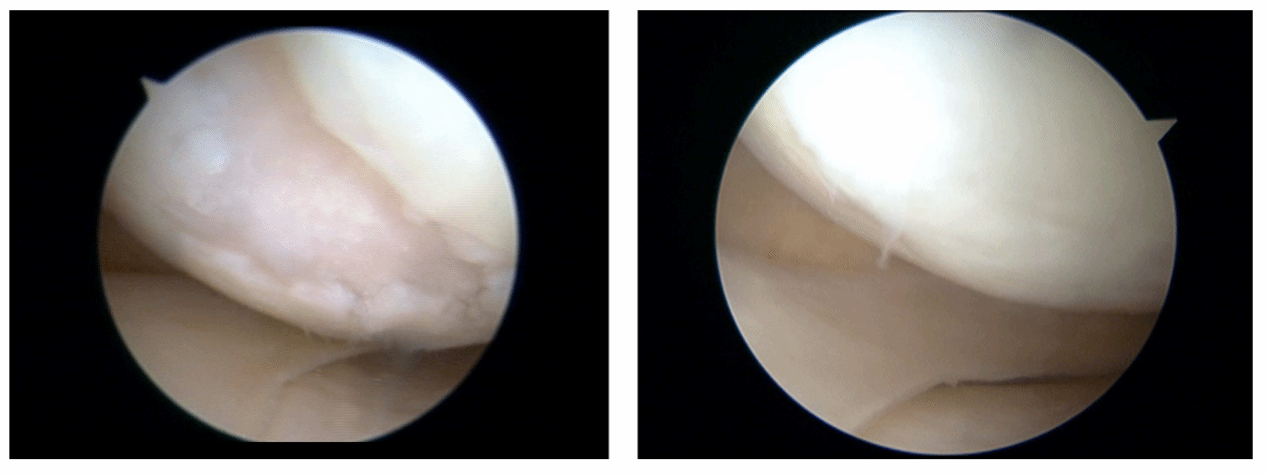

胫骨高位截骨术后1年,关节镜下软骨和半月板表现